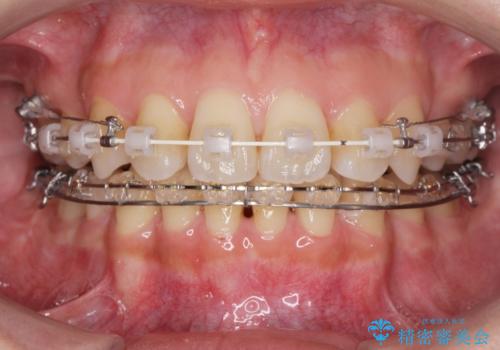

- ワイヤー矯正

- 八重歯・がたつきのある歯並びの改善を求めて来院されました。

全部の歯が入り切るスペースがなかったため、小臼歯4本を抜去しワイヤーを用いたマルチブラケット矯正を選択しました。

歯並びの改善と共に、歯ブラシがしやすくなった!と喜んでいただくことができました。